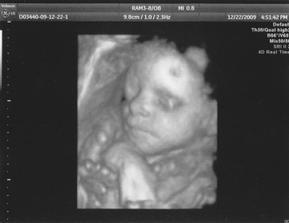

Klárka

Narodila se 15.2.2010 v 15:41 hod. ve Fakultní Thomayerově nemocnici v Praze, vážila 2080 g a měřila 43 cm.